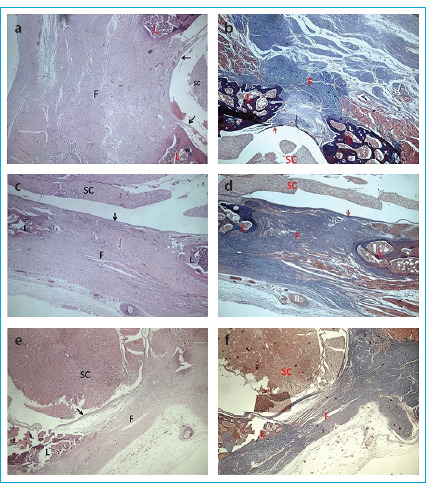

Methods: The rats were randomly assigned to the control, the TM5441, and the TM5484 groups (n=6 per group). In the control group, just a laminectomy was performed. In the treatment groups, intragastric administration of PAI-1 antagonists was done after skin closure. Epidural fibrosis was investigated macroscopically and histopathologically four weeks later.

Results: In the TM5441 and TM5484 groups, the macroscopic epidural fibrosis score was less than the control group (p<0.001 for both groups). Microscopic epidural fibrosis score was also decreased in the TM5441 and TM5484 groups (p>0.05 for both groups). Fibroblast cell density classification scores in the TM5441 and TM5484 groups were lower when compared to the control group (p>0.05 for both groups). Fibrosis thickness was lower in the TM5441 and TM5484 groups when compared to the control group (p<0.01 for both groups).

Abstract Image